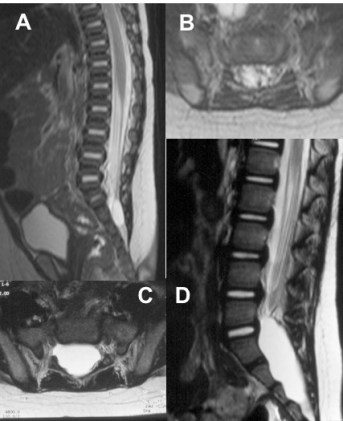

les méningocèles intra-sacrées et kystes de Tarlov

les kystes intra-sacrés sont le plus souvent indolents et stables, ils peuvent

parfois progresser en volume et provoquer des douleurs, justifiant une intervention de résection.

ci-contre : méningocèle intra-sacrée, découverte à la naissance devant une fossette sacrée (A, B) ; progression à 3 ans avec douleurs (C, D)